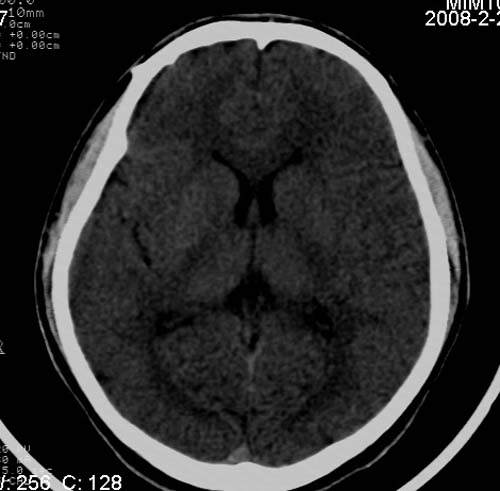

男,17岁,3天前与人斗殴,自述头痛、头晕。无恶心、呕吐,无阳性体征,一般情况良好。

病灶以钙化为主,无明显占位效应,病灶周围无水肿,这种情况应该是脑血管畸形,最多见的是动静脉畸形,其次是海绵状血管瘤.

考虑为:右侧顶叶脑血管畸形。建议:行进一步检查明确诊断。

病人较年轻,有头疼、头晕症状,动静脉畸形可能性大。